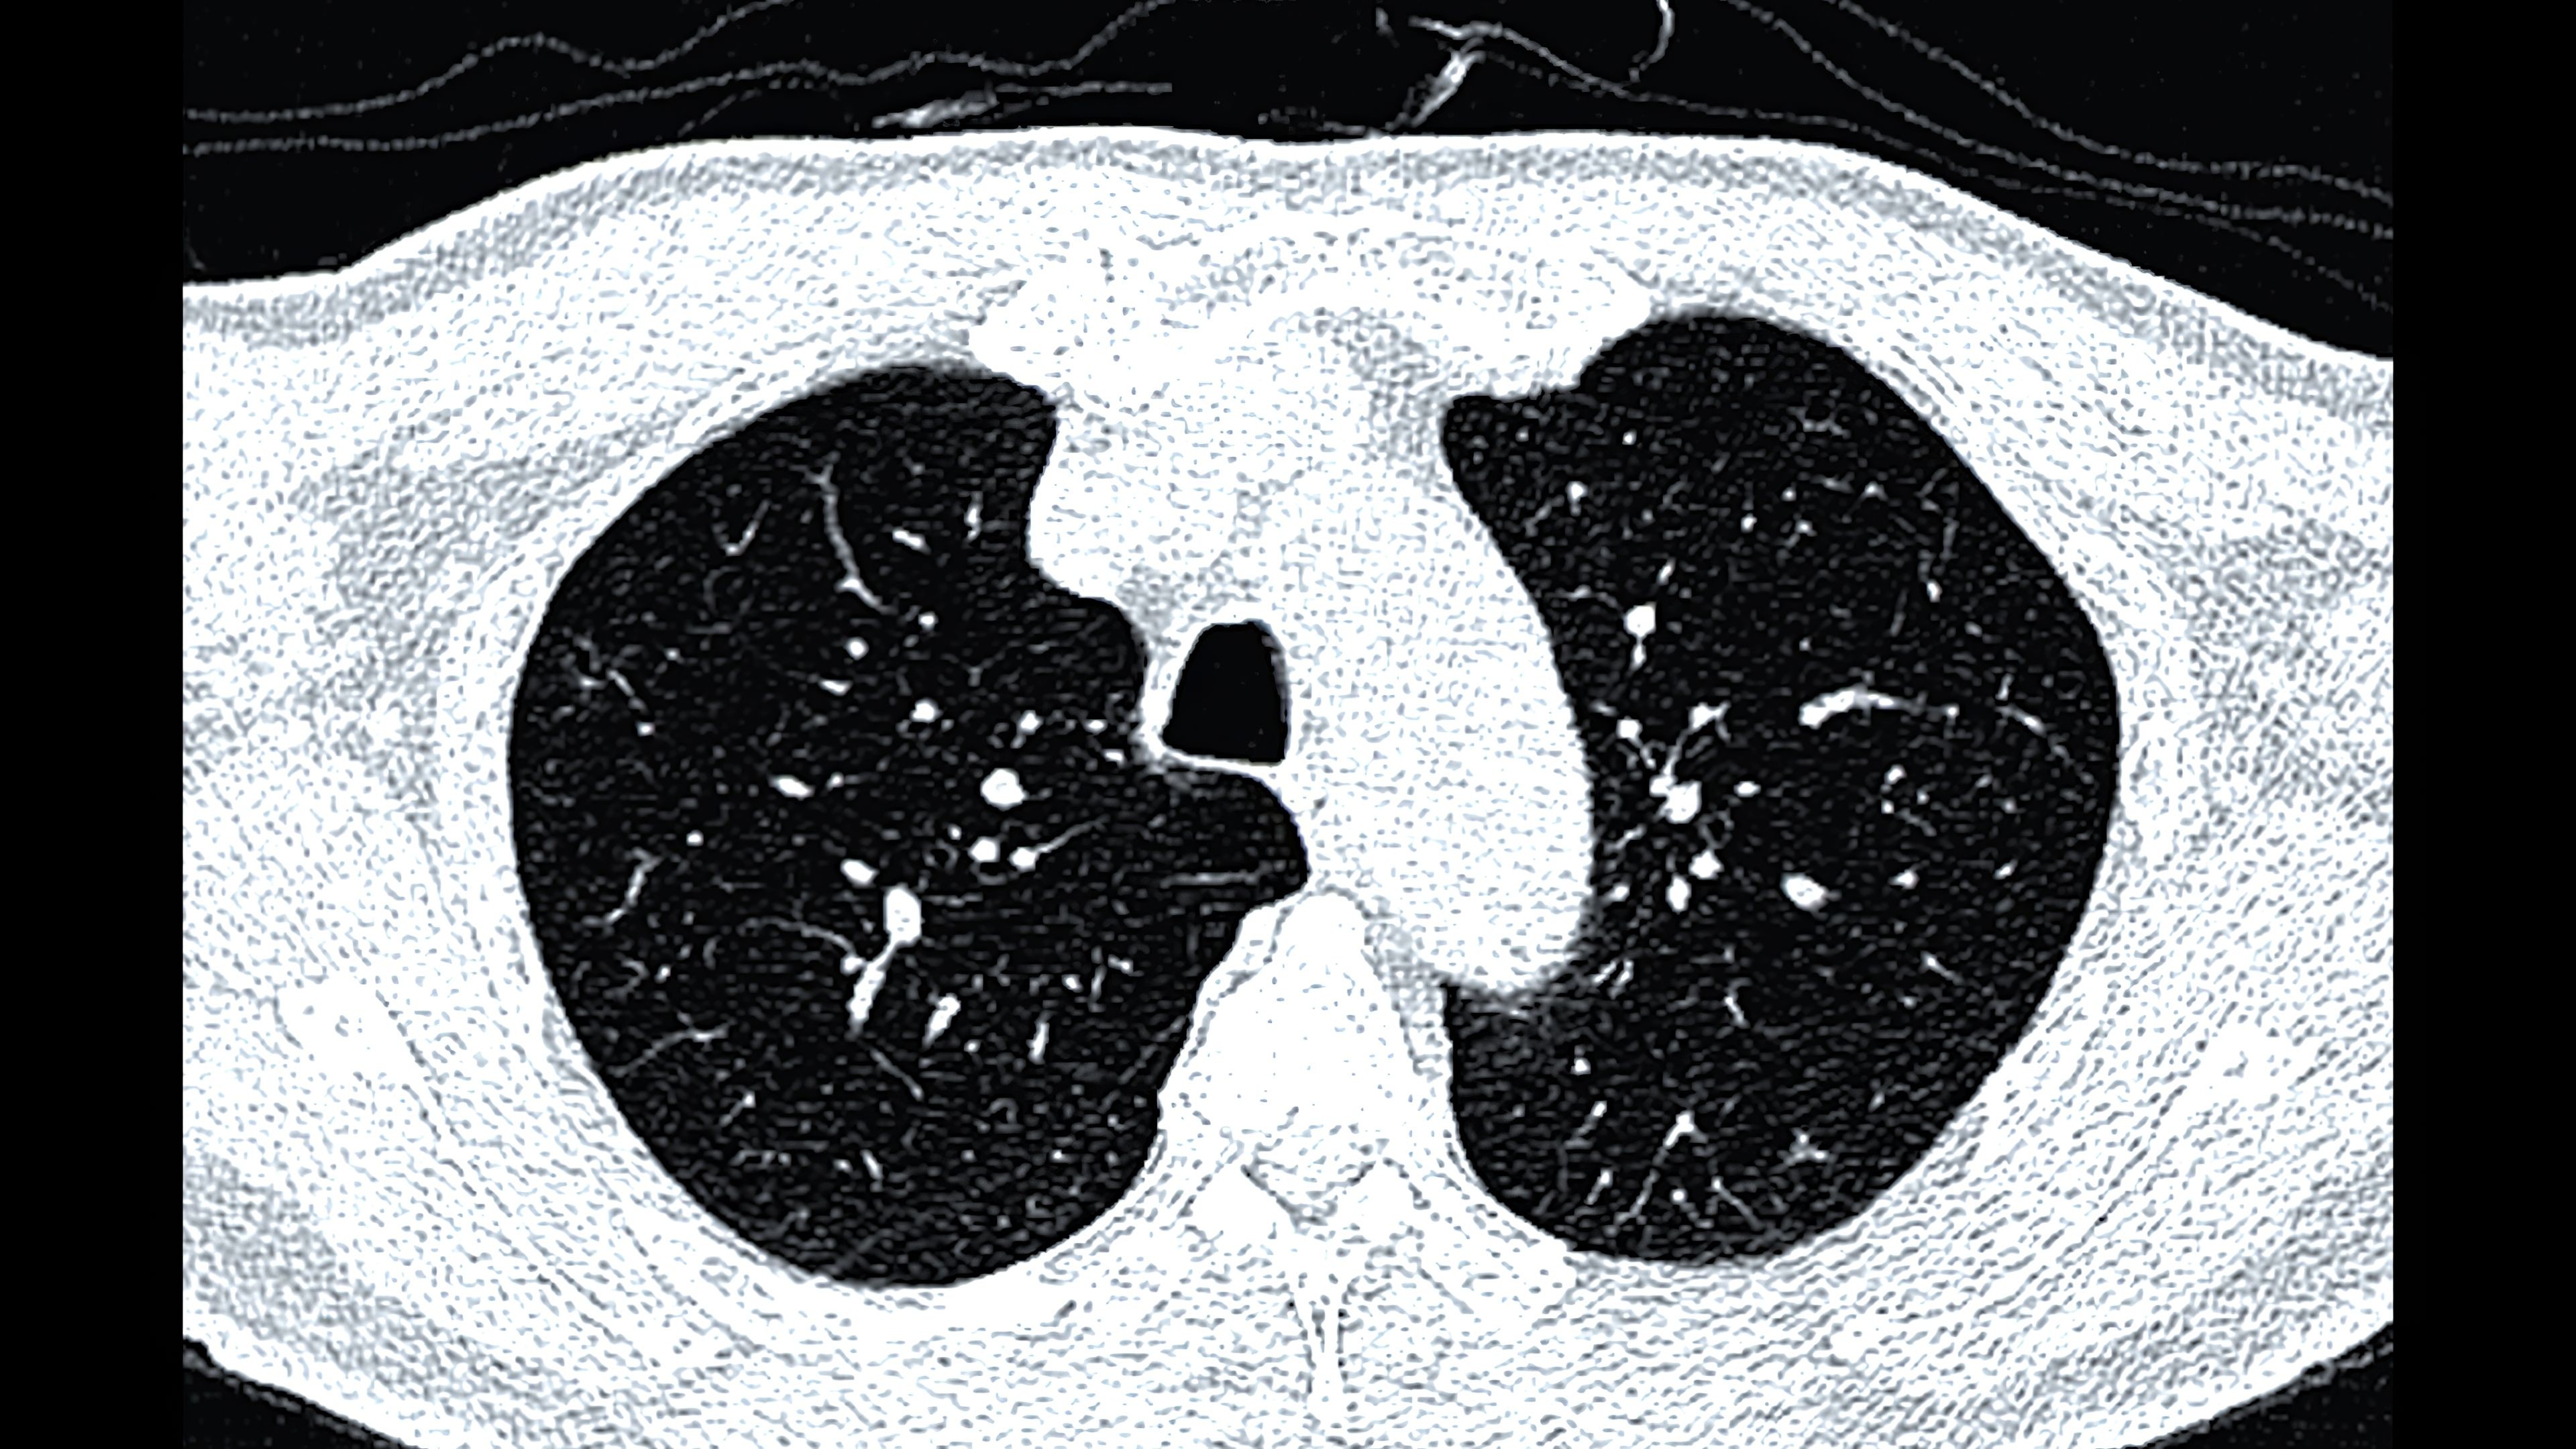

Počet případů tuberkulózy v Česku neklesá. Kvůli měnící se geopolitické situaci sem proudí lidé ze zemí, kde se nemoc vymyká kontrole. Podle aktuálních dat z Národního registru TBC je v ČR historicky nejvyšší podíl nemocných cizinců – 52 procent. Plicní lékaři volají po důkladném a propracovaném záchytu všech, kdo do České republiky přicházejí. Zatím totiž zdravotní prohlídku podstupují pouze ti, kteří zde legálně pracují. Téma pneumologové otevírají při příležitosti Světového dne boje proti tuberkulóze, jenž připadá na 24. března. Ve stejný den o 144 let dříve oznámil německý lékař Robert Koch objev zákeřného bacilu Mycobacterium tuberculosis, jenž nemoc způsobuje.